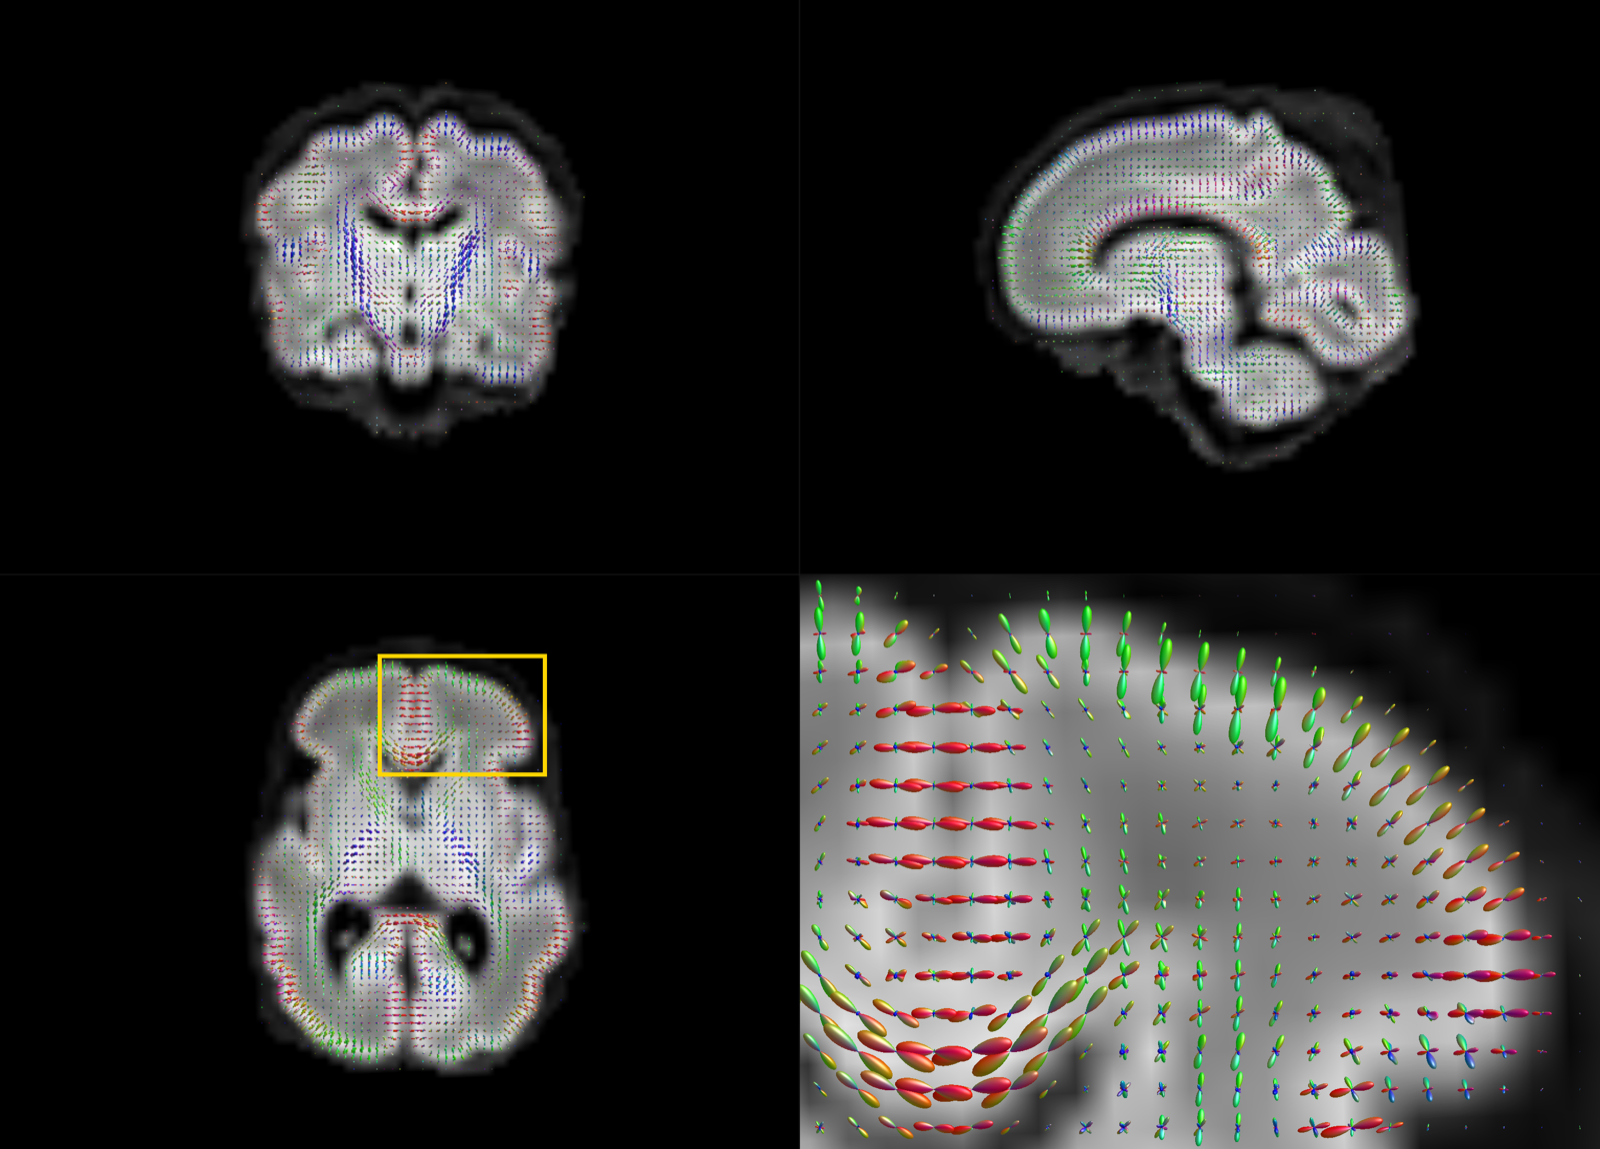

The motion-corrected super-resolved SHARD reconstructions are suitable for a wide range of analyses to explore tissue microstructure and orientation. Figure 9 displays the tissue orientation distribution function (ODF) in each voxel, derived using a group-wise 2-component multi-shell factorization. Specifically, the 5 selected subjects at term were each decomposed into a tissue component (the SH convolution of a tissue response function and ODF at ) and an isotropic () fluid component, using unsupervised convexity- and nonnegativity-constrained spherical factorization (Christiaens et al., 2017). Subsequently, the 2-component spherical deconvolution (Jeurissen et al., 2014) was repeated with the group-average response functions. The figure shows a comparison between scans at both ends of the motion spectrum. In both cases, we retrieve the major developing white matter tracts, including the corticospinal tracts and middle cerebellar peduncles shown in the figure. Figure 10 displays the tissue ODF in a preterm subject, scanned at birth (31 wPMA) and at term-equivalent age (41 wPMA). In this case, we can observe the radial tissue orientation in the developing cortex.